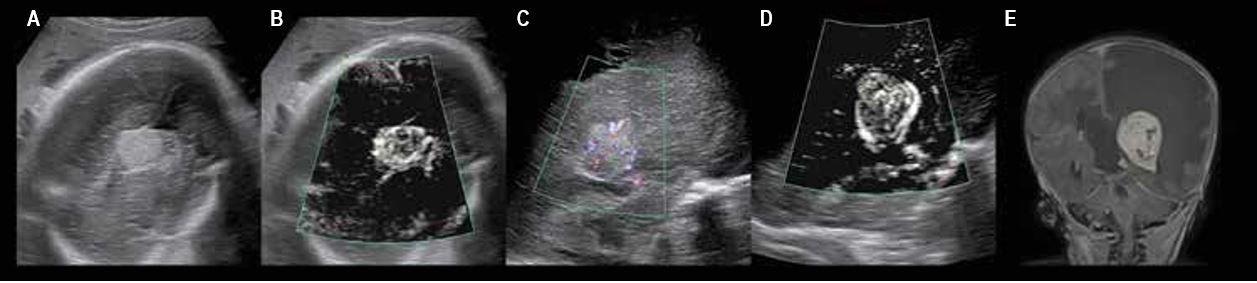

Патологічні зміни судин хоріального сплетення (мал. 5)

Папілома хоріального сплетення — це дуже рідкісна доброякісна пухлина, що добре кровопостачається, та становить менше 1 % пухлин головного мозку. Пік частоти захворювання спостерігається приблизно в 6 місяців.

Про гіперехогенне утворення свідчить вентрикуломегалія або гідроцефалія, що спостерігаються у внутрішньоутробний період.

При цьому в пухлині іноді виявляються мікрокальцифікати або крововилив. Застосування методу ультразвукової візуалізації не завжди можливо для диференціальної діагностики утворень цього виду та папілярної карциноми сплетення. Менінгіома — це пухлина, що дуже рідко зустрічається у дітей.

Мал. 5. Патологічна зміна судин хоріонічного сплетення, нерезектабельна:

A, B, C - пренатальне ультразвукове обстеження на 32-у тижні вагітності;

D — постнатальне черезтім’ячкове ультразвукове обстеження;

E – постнатальна МРТ; фронтальний зріз T1 після введення контрастної речовини;

гіперваскулярне утворення спричиняє синдром «обкрадання», ускладнений широкими ішемічними ураженнями паренхіми

Порівняння чутливості технології SMI із звичайним енергетичним допплерівським картуванням при візуалізації мікросудин.

При ультразвуковому дослідженні у пре- або постнатальний період візуалізація гіперваскулярного утворення, що спостерігається при МРТ із відстроченим контрастуванням після ін'єкції, можлива лише за допомогою технології SMI.